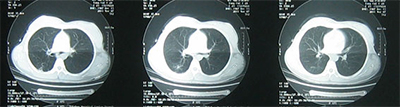

治療一個月后復(fù)查CT示:(2016年2月)